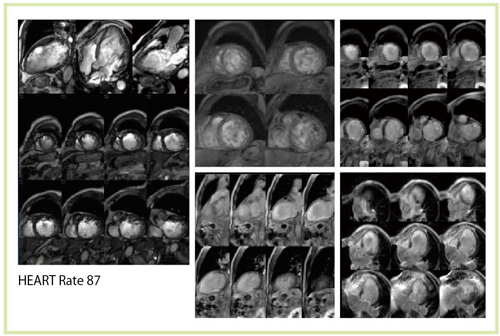

3T MRIによる心臓は,susceptibility artifactの影響やSAR(specific absorption rate)の制約のために,従来は撮像が困難な領域であった。しかし,Titan 3Tでは非常に明瞭な画像が得られている(図5〜8)。

図8 87bpmの高心拍な被検者の心臓MRI(Titan 3T)

心臓MRIにおける3T装置では,1.5T装置で主流となっていたTrueSSFP法が利用しづらい。これは静磁場とRF磁場の不均一や,SARの制約を受けるためである。3T装置によるシネMRIでは,susceptibility artifactやbanding artifactが目立つようになる(図9)。この問題については,中心周波数(f0)をシフトさせることで,アーチファクトを抑えるといった回避策が考え出された。中心周波数(f0)を0ppm,1.0ppm,1.5ppmと変化させると,図10のようにbanding artifactが画面上方にシフトすることがわかる。心臓の場合,関心領域が狭いので,心臓以外にbanding artifactをずらすことで,良好な画像を得ることができる(図11)。

しかし,まだ改善の余地も残されている。例えば,心筋perfusion MRIの場合,TrueSSFP法を用いると局所磁場不均一による擬似defectが出現し,画質不良となる。そのため,現状ではIR-FFE法で代用している。一方,心臓MRIにおける3T装置では,組織のT1緩和時間が延長することで,tagging法における標識が長時間持続するという大きな特徴がある(図12)。